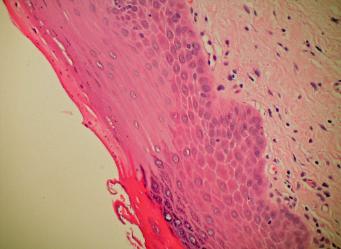

Porokeratosis